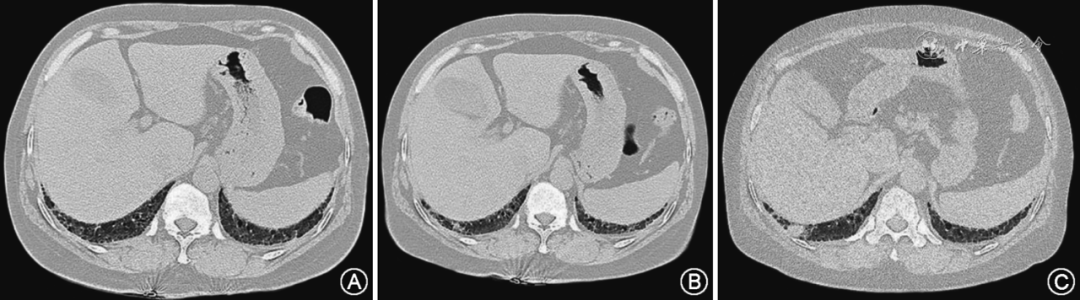

二 肺癌合并间质性肺疾病的危险因素及发病机制 【推荐意见1】肺癌和间质性肺疾病具有相似的危险因素,男性、吸烟、高龄是肺癌合并间质性肺疾病的危险因素,建议高危人群密切随访,警惕共病的发生(Ⅱ级证据,共识比例100%,A级强烈推荐)。 肺癌和间质性肺疾病有共同的危险因素,吸烟是肺癌公认的独立危险因素,同时烟雾可以引起成肺纤维细胞生长增殖,吸烟作为间质性肺病等慢性呼吸系统疾病的危险因素也逐渐得到认可。病例对照研究显示,有吸烟史IPF患者的肺癌发生风险明显增加,尤其是吸烟指数>400的IPF人群,吸烟是肺癌合并间质性肺疾病的危险因素。除了吸烟,高龄患者也是LC-ILD的高危人群,IPF患者中年龄>60岁与LC相对风险为2.41。此外,男性也是LC-ILD的高危人群,IPF患者中男性与LC相对风险为11.04。一个纳入35项研究的荟萃分析显示,男性、吸烟IPF患者的肺癌患病率明显升高。因此,间质性肺疾病患者,尤其对于老年、男性、吸烟的间质性肺疾病患者,要加强随访密切监测,警惕肺癌的发生。一项回顾性研究显示用力肺活量(forced vital capacity,FVC)快速下降、一氧化碳弥散量(diffusing capacity of the lungs for carbon monoxide,DLCO)降低是肺癌合并间质性肺疾病的危险因素,建议间质性肺疾病患者定期进行肺功能检查。 【推荐意见2】肺癌和间质性肺疾病的发生发展是多因素参与的复杂过程,两者存在共同的发病机制,主要有遗传易感性、表观遗传学、异常信号通路和上皮细胞-间充质转化等,建议深入开展基础研究,探索共病发生机制(Ⅳ级证据,共识比例100%,B级中等推荐)。 在遗传易感性方面,肺癌和间质性肺疾病的发生和发展过程中存在相同的基因突变。IPF患者的上皮损伤及修复可引发p53基因突变,出现化生和不典型增生,导致肺癌的发生。另有研究显示KRAS、MET在LC及IPF患者中存在突变和表达改变,可能导致肺癌合并间质性肺疾病的发生。在表观遗传学方面,IPF和LC组织中均有微小RNAs miR-21上调,miR-21介导成纤维细胞的活化和肺纤维化,miR-21表达增加还与肺癌发生有关;另有研究发现在IPF和LC肺组织中同时出现miR-29、miR-30、miR-185表达变化,特定microRNA的异常表达与LC-ILD发生有关。此外,磷酯酰肌醇-3-激酶(phosphatidylinositol 3 kinase,PI3K)/蛋白激酶B、转化生长因子-β(transforming growth factor-β,TGF-β)通路等信号传导通路的异常激活参与了ILD和LC的发病过程。上皮-间质转化(epithelial mesenchymal transition,EMT)是IPF发病的一个重要特征,EMT也是肿瘤发生、发展及侵袭过程的关键特征,在肺癌合并IPF的发病中发挥重要作用。肺癌和间质性肺病存在共同的发病机制,是肺癌合并间质性肺病共病发生的基础。 三 间质性肺疾病的肺癌筛查与管理 【推荐意见3】明确诊断为ILD患者,在ILD规范治疗的基础上,应每年进行肺部高分辨薄层CT检查,如果发现肺部结节,建议根据结节大小、结节部位、危险程度及并发症发生风险,选择密切观察或者微创活检或者手术切除,尽可能实现肺癌的早期诊断(Ⅳ级证据,共识比例100%,B级中等推荐)。 ILD患者的肺癌病灶以结节影最为常见,实性结节为主,依次为部分实性结节及磨玻璃结节。共病患者肺癌可有分叶征、毛刺征及胸膜牵拉等典型肿瘤特征,但大部分肺癌病灶呈不规则形状,有研究显示57.1% 共病患者的肺癌病灶有支气管充气征,10.7% 肺癌病灶有空腔、空洞,对于间质性肺疾病患者胸部CT出现空腔、空洞的实性结节,要警惕合并肺癌的可能。共病患者肺癌大部分出现在肺间质病变区域,或毗邻部位,少部分在正常肺组织。日本的一项临床研究将ILD分为UIP组(临床IPF组)、非UIP组(临床非IPF组),随访结果显示在UIP组中,肺癌多发生于肺下叶胸膜下(75.5%),与UIP的分布相匹配;在非UIP组中,肺癌多发生于肺上叶(68.1%)。 由于间质性肺疾病的存在,早期肺癌病灶不易发现,且形态不规则(图1),容易出现漏诊及误诊,因此间质性肺疾病患者肺结节的早期筛查尤为重要。明确诊断ILD的患者应定期复查,建议每年一次高分辨率薄层肺部CT作为筛查方法。如果ILD患者肺部CT发现肺部结节,可根据结节的密度、结节的大小、结节的恶性风险评估,通过多学科会诊,选择密切观察或者微创活检或者手术切除,ILD患者的肺结节管理流程见图2。 图1 间质性肺疾病-早期肺结节-确诊肺癌的影像学变化 注:图A为2023年6月肺部CT提示间质性肺疾病;图B为2024年6月肺部CT显示右肺下叶新增结节;图C为2024年12月肺部CT显示右肺下叶结节增大,组织病理提示低分化肺癌 图2 ILD患者的肺结节管理流程图 对于高度可疑恶性结节,可以选用手术切除或微创活检以明确诊断。微创活检主要有支气管镜检查、超声支气管镜引导下经支气管针吸活检术(endobronchial ultrasound-guided transbronchial needle aspiration,EBUS-TBNA)、CT引导下经皮胸部穿刺活检(CT-guided transthoracic core needle biopsy,TTNB)检查等。中央型病灶通常采用常规支气管镜检查,周围型病灶多选用TTNB检查作为活检方法,既往研究显示间质性肺病患者的肺癌以外周分布为主,一项TTNB应用于IPF患者肺结节研究显示,TTNB诊断的敏感性和特异性分别为90%和84%,与单纯肺结节诊断相仿,但并发症高达51%,12%患者因气胸需要行胸腔闭式引流术,沿进针路径有蜂窝状结构是气胸发生的独立危险因素,对于穿刺路径存在蜂窝状结构的ILD患者在TTNB检查时要评估气胸的风险,警惕并发症的发生。此外,一些支气管镜新技术,如导航支气管镜、超细支气管镜对于肺外周结节有较好的诊断价值,可作为间质性肺病患者肺结节的诊断方法。 共识建议ILD患者定期随访,每年进行肺部HRCT检查,如果发现肺部结节,根据结节大小及危险程度进行密切观察、微创活检或手术切除。ILD患者肺癌影像不典型,直径>8 mm的实性结节或者实性成分>8 mm的混合密度结节,可以进行PET-CT检查,提高共病患者早期肺癌诊断的准确率。 四 肺癌合并间质性肺疾病中肺癌的组织病理学检查 【推荐意见4】肺癌合并间质性肺疾病患者应积极进行组织病理学检查,明确共病患者的病理类型、驱动基因状态、免疫治疗生物标志物表达(Ⅱ级证据,共识比例100%,A级强烈推荐)。 研究显示LC-ILD患者肺癌病理类型以非小细胞肺癌为主,其中鳞状细胞癌是LC-ILD 最常见的病理类型,一项纳入8个国家6384例肺癌合并ILD的荟萃分析显示鳞癌占37.82%、腺癌占30.79%、小细胞肺癌占20.48%、大细胞肺癌占5.21%。此外,有研究显示肺腺癌和小细胞肺癌的发生呈上升趋势。另有研究指出LC-ILD的肺癌病理类型与ILD的种类有关联性,在普通间质性肺炎患者(usual interstitial pneumonia,UIP)型ILD中,肺鳞癌是最常见的病理类型,在非UIP型ILD中,肺腺癌是最常见的病理类型。 LC-ILD患者中EGFR突变、ALK或ROS重排等常见驱动基因突变率低。一项LC-ILD队列研究中,有治疗意义的驱动基因突变比率为17.19%。日本系列回顾研究显示,NSCLC-ILD患者和单纯NSCLC患者的EGFR基因突变率分别为0~5.8%及 24.3%~47%,多变量分析显示EGFR突变与不存在ILD独立相关。LC-ILD患者EGFR驱动基因突变比率低的原因,可能与LC-ILD患者中男性、吸烟及鳞癌占比高有关。有研究显示程序性细胞死亡配体1(Programmed cell death-ligand 1,PD-L1)在LC-ILD中表达升高,LC-ILD患者PD-L1阳性表达率为40%~61%。本共识建议明确LC-ILD患者的肺癌病理类型、驱动基因状态、免疫治疗生物标志物,有助于肿瘤治疗方案的选择与制定。 五 肺癌合并间质性肺疾病的治疗总策略 【推荐意见5】在ILD病情稳定前提下,应根据患者的肺癌病理类型、临床分期、体能状态、驱动基因状态、免疫治疗生物标志物、治疗相关肺损伤发生风险,选择适合的肿瘤治疗方案(Ⅱ级证据,共识比例100%,A级强烈推荐)。 肺癌进展是导致LC-ILD患者死亡的主要原因,因此需要积极进行抗肿瘤治疗。肺癌治疗方案有手术、放疗、化疗、靶向治疗、免疫治疗等多种方案,LC-ILD特别是合并IPF的患者,通常年龄较大,基础疾病多,生存状态(Performance status,PS)评分差,限制了抗肿瘤方案的选择。在ILD病情稳定前提下,应根据患者的肺癌病理类型,临床分期,体能状态,驱动基因状态,免疫治疗生物标志物权衡利弊选择个体化肿瘤治疗方案。 ILD急性加重(acute exacerbation,AE-ILD)也是导致LC-ILD患者死亡的主要原因。肺癌化疗、放疗、化疗、靶向治疗均有导致AE-ILD的风险。多项研究显示,非手术区域的肺纤维化会增加肺癌合并ILD患者术后AE-ILD的发生风险,先前存在ILD是肺癌放疗发生放射性肺炎的危险因素,既往存在ILD与EGFR-TKI靶向药物治疗相关ILD具有相关性,真实世界研究显示ILD病史是ALK-TKI治疗相关ILD的危险因素。肺癌治疗会增加LC合并ILD患者间质性肺病急性进展的风险,建议综合肿瘤治疗获益和潜在治疗不良反应,选择适当的肿瘤治疗方案。 六 肺癌合并间质性肺疾病的具体治疗方案 【推荐意见6】早期肺癌合并ILD患者,应充分进行围手术期风险评估,严格把控手术指征,权衡患者的手术获益及并发症发生风险,通过MDT讨论决定手术方式及切除范围,并做好围手术期管理(Ⅱ级证据,共识比例100%,A级强烈推荐)。 手术是早期非小细胞肺癌有效的治疗方法,外科切除是Ⅰ、Ⅱ期NSCLC首选治疗方式,ⅢA期和部分ⅢB期可切除的NSCLC推荐以外科为主的综合治疗。对于有手术指征的早期肺癌合并ILD患者,需要充分评估围手术期风险,进行全身重要脏器评估,排除器官严重合并症。重点对患者进行心肺功能评估,推荐使用心电图、心脏超声、动脉血气和肺功能检查。肺癌合并间质性肺疾病患者,肺功能以限制性通气功能障碍为主,早期可出现弥散功能可降低,DLCO下降。围手术期气道管理专家共识对于肺弥散功能的手术风险评估指出,DLCO占预计值%>80%为手术低风险,DLCO占预计值%为40%~79%为手术中风险,DLCO占预计值%<40%为手术高风险,术前通过对LC-ILD患者肺功能及重要脏器进行评估,谨慎选择手术治疗。 肺癌手术方案需参照肿瘤大小及部位制定,早期肺癌手术切除主要有根治性外科切除手术、解剖性肺段切除手术、楔形切除手术等。根治性外科切除手术是早期NSCLC首选治疗方案;亚肺叶切除中解剖性肺段切除手术适用于患者无法耐受肺叶切除,或者肿瘤长径≤2 cm的周围型小结节;楔形切除手术推荐适用于病灶位于肺外周1/3,实密成分≤0.5 cm,长径≤2 cm 的小结节。CALGB140503研究发现在IA期NSCLC(肿瘤≤2 cm)中,亚肺叶切除与肺叶切除5年总生存期(overall survival,OS)及5年无病生存率(disease-free survival,DFS)无显著差异,且亚肺叶组的肺功能保留较肺叶切除组有优势。JCOG0802结果显示,对于≤2 cm、薄层扫描CT上实性成分占比(consolidation tumor ratio,CTR)>0.5的早期肺癌,肺段切除组较肺叶切除组有更多的肺功能保留,但两组的无复发生存时间(relapse free survival,RFS)并没有显著差异。 肺癌合并LID患者,与不合并LID的肺癌患者相比,整体手术预后欠佳。一项大型队列研究比较LC-ILD患者和单纯LC患者术后五年生存率,结果显示两组ⅠA期、ⅠB期、ⅡA期、ⅡB期、ⅢA期、ⅢB期五年生存率分别为59%比86.8%,42%比73.9%,43%比61.6%,29%比49.8%,25%比40.9%,17%比27.8%,LC-ILD组患者肺癌术后病死率高,预后欠佳。一项纳入870例接受手术治疗的肺癌患者研究结果显示,肺癌合并IPF患者手术相关死亡率高于单纯肺癌患者(7.1% 比1.9%,P=0.030),肺癌合并ILD术后病死率高的原因主要在于发生AE-ILD。 一项Meta分析纳入12项研究共2 655例LC-ILD患者,探讨术后AE-ILD发生的危险因素,结果显示男性、CT表现为普通型间质性肺炎、涎液化糖链抗原(KL-6)水平升高、C反应蛋白水平升高、乳酸脱氢酶水平升高等是术后AE-ILD发生的危险因素。另有多项研究显示高龄(年龄>70岁),PS评分>1分,ILD类型为IPF,CT显示蜂窝型,FVC<70%,有非手术区域的肺纤维化等,会增加LC-ILD患者术后AE-ILD的发生风险。此外,术后AE-ILD的发生也与手术方式、手术范围、手术时间等因素相关。6项研究纳入576例LC-ILD患者,报道了手术时间与肺癌术后AE-ILD的关系,显示手术时间延长是AE-ILD发生的危险因素(WMD=28.26,95%CI:1.13~55.39,P=0.041)。9篇文献包含2 527例LC-ILD患者研究手术方式与肺癌术后AE-ILD的关系,结果显示亚肺叶切除(如楔形切除术)患者发生AE-ILD的风险较低,肺叶切除术导致AE-ILD发生率是楔形切除术的5.7倍,手术范围越大术后AE-ILD发生率越高(OR=2.31,95%CI:1.42~3.77,P<0.001)。另一项研究纳入1 763例肺癌合并间质性肺病患者,结果显示,与肺叶切除术组相比,虽然楔形切除术组患者的AE发生率较低,但肺癌复发率较高,预后比肺叶切除术差。另有研究报道手术前高浓度氧疗也是LC-ILD术后AE-ILD发生的危险因素。4项研究提取了248例LC-ILD的肺癌位置数据,结果显示无论肺癌位于左肺叶还是右肺叶,LC-ILD患者肺癌切除术后AE-ILD的发生率无显著差异(OR=1.29,95%CI:0.51~3.24,P=0.594)。 本共识建议严格筛选LC-ILD手术患者,充分进行围手术期评估,根据共病患者肺癌的分期、位置和患者心肺功能及全身功能状态,在MDT基础上决定手术类型及切除范围,同时在术中及术后进行更仔细的监测、观察与随访,警惕不良反应的发生。 【推荐意见7】肺癌合并ILD患者放射治疗相关肺损伤发生率较高,在ILD病情稳定前提下,仔细评估患者的危险因素,建议多学科讨论,根据肿瘤位置、大小,结合患者肺功能,选择合适的放射治疗方案及剂量(Ⅱ级证据,共识比例97.73%,A级强烈推荐)。 放射治疗可以作为不适合手术或拒绝手术的早期NSCLC治疗选择。放疗主要包括常规放疗、立体定向放射治疗(stereotactic radio-therapy,SBRT)、质子放疗、碳离子放疗等。对于无法手术的Ⅰ、Ⅱ期NSCLC患者,SBRT引起放射性肺炎(radiation pneumonitis,RP)发生率低,优于传统的常规放疗,SBRT已经成为不能手术的早期NSCLC的重要治疗选择。有研究比较LC-ILD组与单纯LC组接受SBRT治疗的中位生存期分别为27.4个月和 34.8个月(P=0.17),两组中位生存期无统计学差异。系统性综述显示NSCLC合并ILD患者接受SBRT、粒子束治疗或射频消融治疗相关毒性和ILD特异性毒性增高。一项242例接受SBRT治疗LC-ILD患者的回顾性研究发现,严重放射性肺损伤(radiation-induced lung injury,RILI)的发生率为12.4%。另有研究发现在接受SBRT的患者中,LC-ILD组和单纯LC组的≥2级RP发生率分别为20.5%和5.8%(P<0.01),≥3级的RP的发生率分别为10.3%和1.0%(P<0.01),LC-ILD患者放疗所致RP发生率升高,严重可危及患者生命。危险因素研究显示患者FVC<70%,>10%接受辐射的正常肺,PS评分2~4分,鳞状细胞癌,临床分期T2等是LC-ILD患者发生RP宿主方面的危险因素。放疗方面,前瞻性研究发现当照射剂量学参数V20<22%时很少出现RILI;当V20在22%~31%时,8%的患者发生2级RILI;当V20>40%时,3~5级RILI发生率为23%。此外,多项研究证实LC-IPF患者放疗相关RP的发生率明显升高,LC-IPF患者的病死率增加,LC-IPF患者放疗可能弊大于利,欧洲癌症研究与治疗组织建议LC-IPF患者应避免采用放射治疗。临床医师在放疗前应仔细评估患者的肺功能及危险因素,选择合适的放疗方案及剂量。 一项回顾性研究评估LC-ILD患者碳离子放射治疗的安全性,结果显示患者3年及5年总生存率为46.3%及30.4%,AE发生率较低。质子治疗主要优势在于散射辐射量较低,适用于早期肺癌和中央型肺癌患者。有学者认为质子治疗Ⅰ期NSCLC-ILD疗效好,毒性低,对肺部损伤小。但另有文献报道LC-ILD患者接受质子治疗疗效不佳,质子治疗对LC-ILD患者的疗效有待临床试验证实。 LC-ILD患者放疗所致放射性肺炎的危险因素主要有宿主因素,照射剂量、体积、放疗技术计量分割等,本共识建议仔细评估患者的肺功能及危险因素,慎重权衡放疗的获益和不良反应,通过MDT讨论,选择合适的放射治疗方案。质子、碳离子放疗等技术对于LC-ILD患者的疗效及安全性有待进一步验证。 【推荐意见8】化疗是驱动基因野生型LC-ILD患者有效的一线治疗方案,建议在ILD病情稳定前提下,根据肺癌病理类型、临床分期、PS评分,选用适当的含铂双药或去铂单药方案化疗(Ⅱ级证据,共识比例95.45%,A级强烈推荐)。 1. NSCLC-ILD患者的一线化疗 一项Meta分析纳入21篇文献共684例驱动基因阴性的NSCLC合并ILD患者,一线化疗的合并客观缓解率(objective response rate,ORR)为43.0%,合并疾病控制率(disease control rate,DCR)为80.0%,1年OS率为33.0%(95%CI:29.0%~37.0%),合并AE-ILD发生率为8.07%(95%CI:6.12%~10.26%),驱动基因阴性NSCLC-ILD患者一线化疗有效,AE-ILD发生率可接受。前瞻性临床试验探索晚期驱动基因阴性NSCLC-ILD患者一线使用化疗药物的有效性及安全性,结果显示NSCLC-ILD组一线化疗的ORR、PFS与单纯NSCLC组无显著差异,化疗是驱动基因阴性NSCLC-ILD患者有效的一线治疗方法。 化疗方案是NSCLC-ILD患者发生化疗相关不良反应的影响因素之一。一项研究纳入39例铂类联合吉西他滨一线治疗NSCLC-ILD患者,结果显示吉西他滨组AE-ILD发生率为12.6%。一项纳入53例LC-ILD患者的化疗方案研究显示,多西他赛引起的不良事件多于其他化疗方案(18.4% 比5.2%)。对NSCLC-ILD一线化疗方案分层研究的荟萃分析结果显示,紫杉醇(白蛋白结合型)治疗组AE-ILD发生率低于其他化疗方案组(4.98% 比11.92%,P=0.018)。2项评估铂类联合紫杉醇(白蛋白结合型)一线治疗驱动基因阴性NSCLC-ILD患者疗效及安全性的前瞻性试验结果表明:纳入94例NSCLC-ILD患者使用铂类联合紫杉醇(白蛋白结合型)一线治疗NSCLC-ILD的OS达到15.4个月,4例患者(4.3%)出现了AE-ILD;纳入36例NSCLC-ILD患者使用铂类联合紫杉醇(白蛋白结合型)一线治疗NSCLC-ILD的OS同样可达15.4个月,AE-ILD发生率为5.6%,铂类联合紫杉醇(白蛋白结合型)一线治疗驱动基因阴性NSCLC-ILD有较好的生存获益和较低的AE-ILD发生率,是NSCLC-ILD患者安全有效的一线化疗方案。除了化疗方案之外,ILD类型也是化疗后AE-ILD发生的危险因素,有研究者回顾性分析了109例LC-ILD患者,发现合并UIP模式的肺癌患者比合并非UIP模式的肺癌患者化疗相关AE-ILD发生率更高(30%比8%,P=0.005),合并UIP模式的肺癌患者化疗有更高的AE-ILD病死率。 2. NSCLC-ILD患者的二线化疗 系列研究中31.6%~72.2%的NSCLC-ILD患者接受了二线化疗,患者的PFS为1.2个月,OS为4个月。有研究纳入104例NSCLC-ILD患者,发现NSCLC-ILD患者OS低于不合并ILD的NSCLC患者,二线化疗中有较高的AE发生率。在NSCLC-ILD二线化疗中,使用紫杉醇化疗的AE-ILD发生率从一线治疗的8.3%上升至15.2%。回顾性研究显示,培美曲塞二线治疗NSCLC-ILD组和单纯NSCLC组化疗相关肺损伤发生率分别为12% 和1.1%,二线化疗明显增加NSCLC-ILD患者药物相关肺损伤的发生率。 3. SCLC-ILD患者的一线化疗 3项共80例小细胞肺癌合并ILD的一线化疗研究,其中47例患者接受卡铂联合依托泊苷治疗,33例患者接受顺铂联合依托泊苷治疗,结果显示小细胞肺癌合并ILD患者一线化疗的ORR为62.5%~88.2%,DCR为75%~94%,PFS为4.5~5.5个月,OS为7~9个月。另有研究发现依托泊苷联合铂类一线治疗SCLC-ILD的ORR和PFS与单纯SCLC相比无显著性差异,SCLC-ILD患者可以从一线化疗中获益,但是与单纯SCLC组相比,SCLC-ILD组的总OS时间短,多变量分析发现存在ILD是SCLC患者OS较差的独立危险因素。 4. SCLC-ILD患者的二线化疗 有研究发现接受拓扑替康二线化疗的SCLC-ILD患者比仅接受最佳支持治疗的SCLC-ILD患者总生存期延长。但研究者同时发现拓扑替康二线治疗SCLC-ILD的安全性较差,AE-ILD的发生率高达21.7%。另有研究探究紫杉醇二线治疗SCLC-ILD的有效性和安全性,结果表明SCLC-ILD患者使用紫杉醇治疗具有较好的疗效,但是AE-ILD发生率明显升高,SCLC-ILD患者从二线化疗中受益有限,未来需要开展进一步临床试验研究AE-ILD发生的危险因素。 驱动基因野生型LC-ILD患者一线化疗的ORR、PFS与单纯肺癌患者无显著差异,化疗是LC-ILD患者有效的一线治疗方法。铂类联合紫杉醇(白蛋白结合型)一线治疗驱动基因野生型NSCLC-ILD有较好的生存获益和较低的AE-ILD发生率,本共识推荐其作为驱动基因野生型NSCLC-ILD患者一线化疗方案。SCLC-ILD患者可以从一线依托泊苷联合铂类化疗中受益。二线化疗明显增加LC-ILD患者药物相关肺损伤的发生率,患者从二线化疗中受益有限,需要开展前瞻性临床试验来研究AE-ILD发生的危险因素。 【推荐意见9】LC-ILD患者驱动基因突变率低,且存在TKI相关ILD的发生风险,对于驱动基因突变阳性的LC-ILD患者,尽可能谨慎选用肺毒性低的靶向药物(Ⅳ级证据,共识比例100%,B级中等推荐)。 亚洲NSCLC患者中EGFR突变约占50%,ALK突变占3%~5%,肺癌靶向治疗已经成为驱动基因突变阳性NSCLC的一线标准治疗方案。然而,在NSCLC-ILD患者中驱动基因突变率显著降低,有研究显示不合并ILD的NSCLC患者的EGFR基因突变率24.3%~47%,合并ILD的NSCLC患者的EGFR基因突变率仅为0~5.8%。NSCLC-ILD患者常见驱动基因突变率低,可能与共病患者中吸烟、男性占比高,及鳞状细胞癌是最常见的病理类型有关。 随着靶向治疗的广泛应用,靶向药物性肺损伤越来越受到重视。三项EGFR突变的NSCLC的回顾性队列研究显示,EGFR-TKI诱导的ILD(ET-ILD)发生率为13.6%(95%CI:6.4~20.9)。一项回顾性队列研究显示,EGFR突变的LC-ILD患者,吉非替尼治疗相关的ILD与男性、吸烟史和先前存在ILD显著相关(OR分别为3.10、4.79和2.89)。一项来自真实世界研究发现年龄>55岁、有吸烟史、PS评分2~4分,和既往存在ILD是克唑替尼治疗相关ILD的危险因素,其中既往存在ILD是最关键的危险因素(HR=12.6)。 LC-ILD患者常见驱动基因突变率低,TKI相关ILD的发生风险较高,多项靶向治疗临床试验将ILD患者排除在之外,目前缺乏LC-ILD患者使用TKI的大规模临床研究。本共识建议驱动基因突变阳性LC-ILD患者,尤其对于高龄、有吸烟史、PS评分2~4分的患者,在靶向治疗过程中要警惕TKI治疗相关ILD风险,监测警惕不良反应的发生。 【推荐意见10】VEGF单克隆抗体可以使非鳞非小细胞肺癌合并间质性肺疾病患者获益,应充分考虑VEGF单克隆抗体的适应症和禁忌症,并根据肺癌病理类型和临床分期联合VEGF单克隆抗体治疗,同时密切监测治疗不良反应(Ⅲ级证据,共识比例100%,B级中等推荐)。 血管内皮生长因子(vascular endothelial growth factor,VEGF)在肺癌的发生发展中发挥重要角色。VEGF单克隆抗体药物如贝伐珠单抗目前已批准用于晚期或复发性非鳞非小细胞肺癌的一线治疗。一项前瞻性队列研究及两项回顾性研究均显示卡铂和紫杉醇联合贝伐珠单抗一线治疗非鳞非小细胞肺癌合并间质性肺疾病患者安全有效。回顾性病例对照研究发现在非鳞非小细胞肺癌合并间质性肺疾病患者中,一线化疗联合贝伐珠单抗组比单纯化疗组具有更长的PFS(8.0个月比4.3个月,P=0.026),而且化疗联合贝伐珠单抗组治疗相关AE-ILD的发生率低于单纯化疗组(0比22.6%,P=0.037),VEGF单克隆抗体联合化疗在非鳞非小细胞肺癌合并间质性肺疾病患者中有应用前景。 化疗联合VEGF单克隆抗体可以使非鳞非小细胞肺癌合并间质性肺疾病患者获得疗效及生存获益,并且不增加AE-ILD的发生率,本共识推荐VEGF单克隆抗体联合化疗,作为非鳞非小细胞肺癌合并间质性肺疾病患者的治疗选择之一。 【推荐意见11】肺癌合并ILD患者可以从免疫治疗中获益。在ILD病情稳定前提下,轻度ILD合并肺癌患者可以选用免疫单药或免疫联合治疗,中度重度ILD合并肺癌,尤其为IPF类型患者,应权衡利弊谨慎使用免疫治疗,同时要密切监测免疫治疗相关不良反应(Ⅱ级证据,共识比例100%,A级强烈推荐)。 肺癌已经进入免疫治疗时代,一项Meta分析纳入10项研究共179名LC-ILD患者,免疫治疗LC-ILD的ORR和DCR分别为34%(95%CI:20~47)和66%(95%CI:56~75),与不合并ILD的NSCLC患者相比,LC-ILD组患者的客观缓解率较高(OR:1.99;95%CI:1.31~3.00),但两组的DCR差异无统计学意义(OR:1.46;95%CI:0.94~2.25)。合并或不合并ILD的NSCLC患者的PFS差异无统计学意义,ICIs治疗可以使LC-ILD患者获得疗效获益。 有研究发现与不合并ILD的肺癌患者相比,LC-ILD患者的免疫检查点抑制剂相关肺炎(checkpoint inhibitor-related pneumonitis,CIP)发生率升高。Meta分析结果显示LC-ILD患者中任何级别和3级及以上级别的CIP的发生率为27%(95%CI:17~37)和15%(95%CI:9~22),单纯LC患者中为10%(95%CI:6~13)和4%(95%CI:2~6),LC-ILD患者免疫治疗任何级别和3级及以上CIP的发生率均显著高于单纯LC患者。另有研究发现ICI治疗肺癌合并ILD,增加患者CIP发生的风险,同时会使CIP的发生时间提前。 AMBITIOUS试验是PDL1单抗用于LC-ILD患者的Ⅱ期临床试验,计划纳入38例患者(最终纳入17例患者),≥3级肺炎发生率为23.5%,试验被提前终止,该试验中纳入的LC-IPF患者比例高,导致重度CIP发生率增加。另一项多中心、开放标签单臂Ⅱ期临床试验,纳入18例NSCLC合并轻度特发性间质性肺炎患者,使用PD1单抗治疗,中位随访时间为14.2个月(95%CI:2.7~32.1),ORR为39%,中位PFS为7.4个月(95%CI:1.8~16.8),中位OS为15.6个月(95%CI:14.4-NR),没有3级以上肺炎发生,ICI治疗合并轻度IIP的NSCLC患者安全有效。因此,LC-ILD患者在使用免疫治疗前,建议对间质性肺疾病严重程度进行评估。间质性肺疾病严重程度通常需要结合患者的临床症状、肺功能、影像学表现及预后综合判断,目前尚没有统一的间质性肺疾病严重程度评判标准。GAP指数可以用于评估IPF患者疾病严重程度和预后,经过调整也可用于其他类型ILD的严重程度分层,可按照GAP指数评估LC-ILD患者中ILD的严重程度。Meta分析结果显示GAP 指数高、合并肺癌是IPF患者预后差的危险因素。 ICI治疗可以使LC-ILD患者获得疗效获益,但同时可能增加免疫治疗相关不良反应的发生。肺癌合并轻度ILD(GAP 指数Ⅰ期),共识推荐使用免疫治疗;肺癌合并中度及重度ILD(GAP 指数Ⅱ期及Ⅲ期),尤其为IPF类型,建议慎重选择免疫治疗。肺癌合并ILD患者免疫治疗的同时要密切监测免疫治疗不良反应的发生,做到早发现、早诊断、早治疗。 【推荐意见12】吡非尼酮及尼达尼布有抗纤维化作用,吡非尼酮可降低LC-IPF患者术后AE-IPF发生风险(Ⅲ级证据,共识比例77.27%,C级弱推荐),尼达尼布可能使晚期NSCLC-IPF患者获益,需要开展大规模前瞻性研究来证实抗纤维化药物在LC-ILD患者治疗中的应用价值(Ⅱ级证据,共识比例77.27%,B级中等推荐)。 ILD进展是导致LC-ILD患者死亡的另一原因,在LC-ILD患者肺癌治疗同时应兼顾ILD治疗。吡非尼酮和尼达尼布是目前获批的抗纤维化药物。吡非尼酮具有抗炎、抗纤维化、抗氧化三重阻抗机制,不仅可以有效抑制炎症因子,减轻急性期炎症,而且可以延缓慢性纤维化进展。LC-IPF患者的Ⅲ期临床试验结果显示,吡非尼酮可以延缓IPF患者的疾病进展,已经获批用于治疗IPF。一项研究纳入39例LC-IPF患者,口服吡非尼酮至少2周后进行手术治疗,97.2%患者未发生AE-IPF(38/39,95%CI:85.5%~99.9%,P=0.004),围手术期使用吡非尼酮治疗可以降低LC-IPF患者肺癌术后AE-IPF发生风险。另一项研究纳入31例术前接受吡非尼酮治疗的LC-IPF患者与19例术前未接受吡非尼酮治疗的LC-IPF患者,两组术后30 d AE-IPF发生率分别为0比10.5%(P=0.07),在术后90 d AE-IPF发生率分别为3.2% 比21.1%(P=0.04)。多项回顾性研究证实在围手术期使用吡非尼酮可以降低LC-IPF患者术后发生AE-IPF的风险,可为LC-ILD患者的治疗提供新思路。 尼达尼布是小分子三联血管激酶抑制剂,尼达尼布通过阻止FGF、PDGF和VEGF受体酪氨酸激酶的磷酸化,阻断受体介导的下游信号传导,抑制成纤维细胞的增殖、迁移和转化,有抗纤维化、抗炎作用。尼达尼布已经获批用于IPF、系统性硬化病相关性间质性肺疾病及具有进行性表型的慢性纤维化性间质性肺疾病的治疗。J-SONIC临床研究是第一个肺癌合并IPF的Ⅲ期随机对照试验,旨在评价尼达尼布联合化疗(卡铂联合白蛋白结合型紫杉醇)与单纯化疗(卡铂联合白蛋白结合型紫杉醇)一线治疗晚期NSCLC合并IPF的疗效和安全性,结果显示主要终点无事件生存期EFS,尼达尼布联合化疗组为14.6个月,单独化疗组为11.8个月,(HR=0.89,90%CI:0.67~1.17)。次要终点中位PFS,尼达尼布联合化疗组6.2个月,单独化疗组为5.5个月(HR=0.68,95%CI:0.50~0.92)。在呼吸功能方面,尼达尼布联合化疗组,较单纯化疗组显著抑制NSCLC-ILD患者FVC的下降。 本共识中等推荐尼达尼布用于晚期NSCLC-IPF患者治疗,弱推荐吡非尼酮用于LC-IPF患者围手术期治疗。抗纤维化药物为NSCLC-ILD患者的治疗提供新的思路,需要进一步开展前瞻性临床试验来验证抗纤维化药物在LC-ILD患者治疗中的疗效及获益。 本共识建议ILD患者每年进行高分辨率薄层肺部CT检查及随访,及早发现合并肺癌的共病患者,早期诊断早期治疗是改善LC-ILD患者预后有效的方法。对于有手术指征的LC-ILD,建议通过MDT讨论选择适合的微创手术方式治疗,并做好围手术期管理。卡铂联合紫杉醇(白蛋白结合型)治疗NSCLC-ILD有较好的疗效和较低的AE-ILD发生率,推荐用于驱动基因阴性NSCLC-ILD一线治疗。SCLC-ILD患者可以从一线铂类联合依托泊苷化疗中受益。TKI治疗相关ILD的发生率较高,对于驱动基因突变阳性的LC-ILD患者,谨慎选用肺毒性低的靶向药物。VEGF单克隆抗体联合化疗在非鳞非小细胞肺癌合并间质性肺疾病患者中有应用前景,可根据肺癌病理类型和临床分期联合血管靶向药物治疗。LC-ILD患者可以从免疫治疗中获益,轻度ILD合并肺癌患者可选用免疫治疗,中重度ILD合并肺癌患者应谨慎选用免疫治疗,治疗同时要密切监测免疫相关不良反应的发生。吡非尼酮及尼达尼布有抗纤维化及潜在辅助抗肿瘤作用,未来需要开展大规模前瞻性随机对照临床试验,探索LC-ILD最适合的诊治方案,改善共病患者的生存和预后。 组长:陈良安(解放军总医院第一医学中心) 顾问:(按姓名汉语拼音排序)白春学(复旦大学附属中山医院)、代华平(中日友好医院)、胡成平(中南大学湘雅医院)、黄建安(苏州大学附属第一医院)、李为民(四川大学华西医院)、宋勇(中国人民解放军东部战区总医院)、杨拴盈(西安交通大学第二附属医院)、周建英(浙江大学医学院附属第一医院) 学组专家:(按姓名汉语拼音排序)白莉(陆军军医大学附属新桥医院),陈良安(解放军总医院第一医学中心),程渊(北京大学第一医院),付秀华(内蒙古医科大学附属医院),高蓓莉(上海交通大学附属瑞金医院),韩一平(海军军医大学附属长海医院),何勇(陆军特色医学中心),洪群英(复旦大学附属中山医院),胡洁(复旦大学附属中山医院),姜丽岩(上海市胸科医院),金阳(华中科技大学同济医学院附属协和医院),兰芬(浙江大学医学院附属第二医院),李敏(中南大学湘雅医院),李强(上海同济大学附属东方医院),刘丹(四川大学华西医院),刘晓芳(北京同仁医院),吕镗烽(东部战区总医院),穆传勇(苏州大学附属第一医院),施焕中(首都医科大学附属北京朝阳医院),施敏骅(苏州大学附属第二医院),唐华平(青岛市市立医院),王凯(浙江大学医学院附属第二医院),王珂(吉林大学第二附属医院),王孟昭(北京协和医院),王琪(大连医科大学附属二院),王晓平(中日友好医院),王悦虹(浙江大学医学院附属第一医院),吴迪(深圳市人民医院),谢宝松(福建省立医院),谢敏(华中科技大学同济医学院附属同济医院),徐淑凤(秦皇岛市第一医院),徐小嫚(中国医科大学附属盛京医院),杨侠(西安交通大学第二附属医院),余宗阳(联勤保障部队第九〇〇医院),张艰(空军军医大学西京医院),张晓菊(河南省人民医院),赵微(解放军总医院第一医学中心),钟殿胜(天津医科大学总医院),周承志(广州医学院第一附属医院),周向东(陆军军医大学西南医院),周燕斌(中山大学附属第一医院) 执笔:许阳(解放军总医院第一医学中心),赵微(解放军总医院第一医学中心) 声明: 转载的文章仅用于学术信息传播和学习,版权归原作者和原出处所有,如有侵权请联系删除。